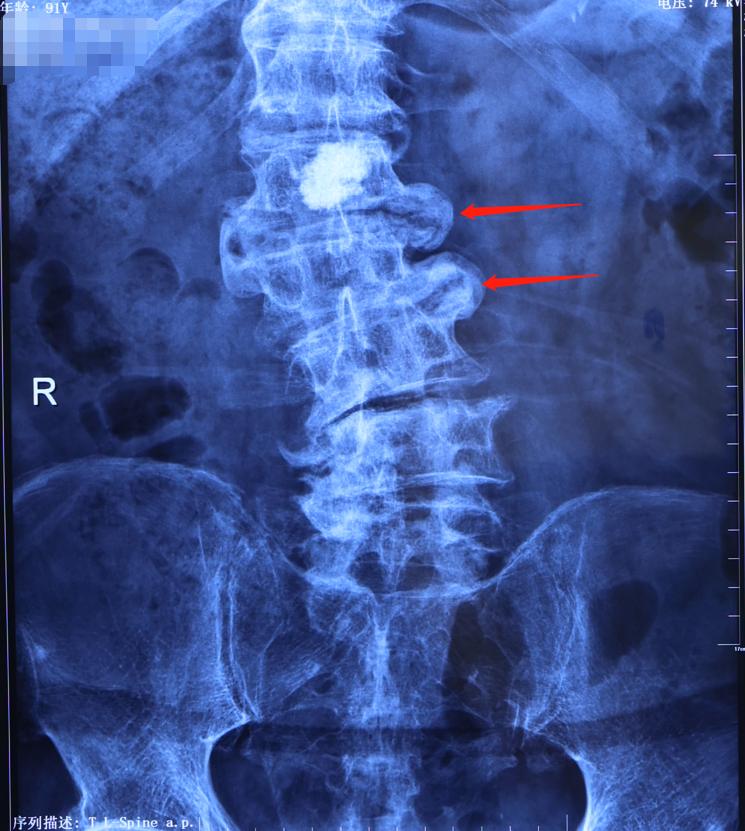

2、发生代偿:腰椎骨桥形成,趋于自稳状态

除此之外,我们还可以看到老人的腰椎体有两个骨桥形成,上下的椎体通过骨桥连接,融为一个。

这种情况就是脊柱趋于自稳状态,是一种代偿反应,原因是为了加固局部椎体的稳定性。上下两个椎体出现增生,各长出骨桥,最后融为一体,使两个椎体成为长到一起。出现这种情况,老年人可能前期会有一些腰痛,走路比较费劲,但是突然有那么几天时间觉得腰不疼了。

为什么这时候反而腰不疼了?这是因为完成了整个腰椎的合拢,腰部的肌肉力量就不用遭受更大的负荷,用来维持冠状位的平衡。那这是不是好事呢?并不!这会加重退变性脊柱侧弯。

3、脊柱侧弯加重:出现神经根受压症状

在上面腰椎退变性侧弯不断加重的过程中,脊柱可能仍然是稳定的,但是在脊柱侧方(凹侧这个地方),就会出现神经根受压,引发一系列症状。

大家可以想象,脊柱本来是垂直的,若两个椎体向中间凹,凹的这一侧神经根孔就会出现狭窄,造成神经根受压。所以这位老人虽然出现这种腰椎骨桥,腰痛虽然有了一定的缓解,但却出现了腿痛,并且腿痛症状日益加重,严重影响到日常生活质量。